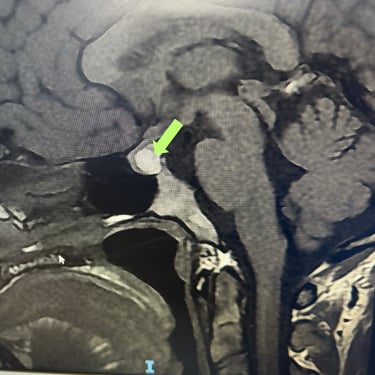

Tumor Selar Hemorrágico: Tratamiento Endoscópico Transesfenoidal.

El tumor selar hemorrágico, también conocido como apoplejía hipofisaria, es una urgencia neuroquirúrgica que puede manifestarse con cefalea intensa, alteraciones visuales y compromiso hormonal agudo. El abordaje mediante cirugía endoscópica transesfenoidal permite un acceso directo y mínimamente invasivo a la región selar, facilitando la evacuación del componente hemorrágico y la resección del tumor. Esta técnica ofrece una adecuada descompresión del quiasma óptico, preservación de estructuras neurovasculares y una recuperación más rápida. El tratamiento oportuno es clave para mejorar el pronóstico neurológico y visual del paciente.